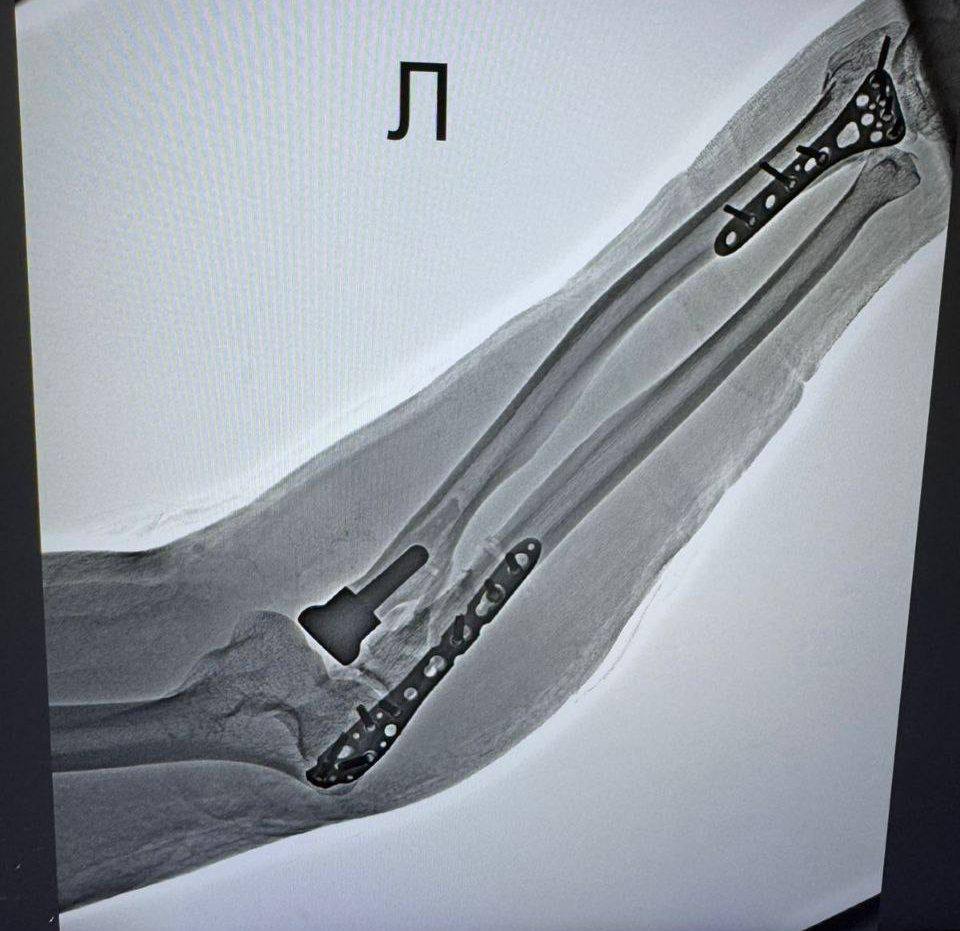

В Наро-Фоминской больнице впервые одновременно провели две сложные операции по установке эндопротезов головки лучевой кости.

66-летняя женщина и 55-летний мужчина поступили с оскольчатыми переломами, полученными при падении. Традиционный остеосинтез был невозможен — хирурги приняли решение заменить повреждённую часть кости эндопротезом.